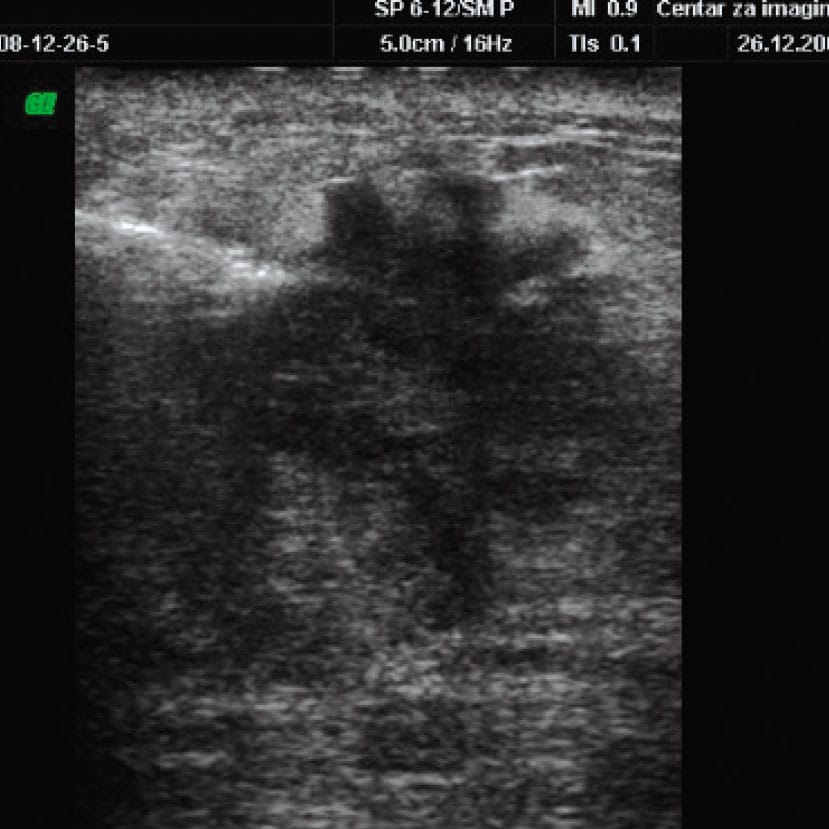

Слика 2. Припрема и извођење кор биопсије промене у дојци под контролом ултразвука.​